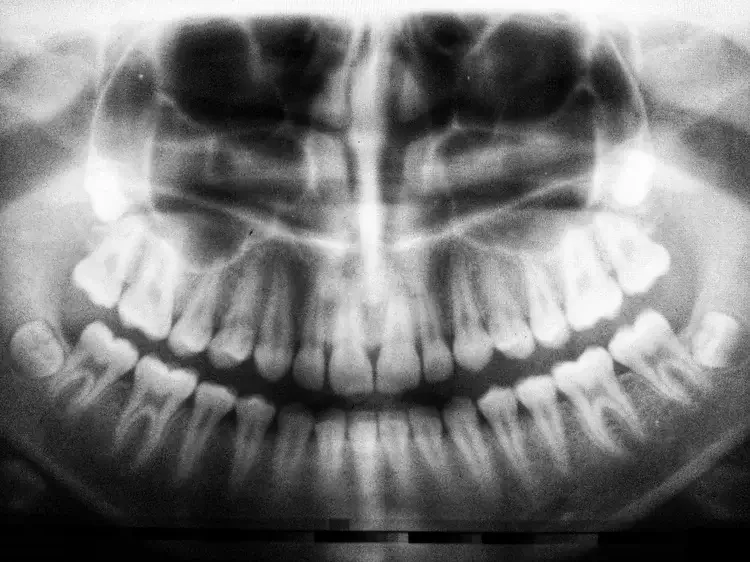

Acudir pronto a un ortodoncista es crucial para detectar dientes que puedan estar atascados o impactados bajo las encías. Los dientes impactados, especialmente los caninos, a menudo pasan desapercibidos sin una evaluación experta y radiografías. Si no se tratan, estos dientes pueden dañar las raíces cercanas o desalinear otros dientes. La detección precoz permite soluciones más sencillas, como crear espacio para guiar el diente a su posición. Esperar demasiado puede llevar a procedimientos más complejos, como la cirugía oral o la extracción del diente. Los ortodoncistas están capacitados para supervisar el desarrollo de los dientes e identificar los problemas antes de que se agraven. Un tratamiento a tiempo puede evitar complicaciones a largo plazo y preservar los dientes naturales de su hijo. Las revisiones periódicas de ortodoncia aseguran que todos los dientes se están desarrollando correctamente y tienen espacio para erupcionar. En Textbook Ortodoncia, utilizamos imágenes avanzadas para evaluar la posición de los dientes y proporcionar una atención proactiva. Una consulta rápida podría hacer toda la diferencia en la sonrisa de su hijo y la salud oral.

Evaluación exhaustiva: Durante la consulta inicial, llevamos a cabo un examen exhaustivo para evaluar las necesidades de ortodoncia de su hijo. Esto incluye radiografías digitales, fotografías, y una discusión detallada de las opciones de tratamiento.